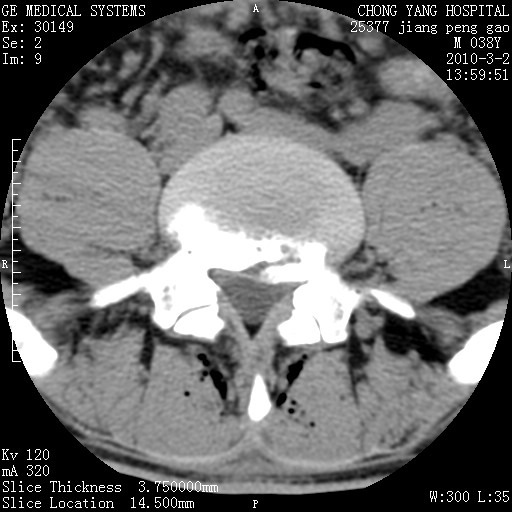

标题: CT24887:M38Y 反复腰痛 无外伤史 未做针灸 竖脊肌为何积气 [打印本页]

标题: CT24887:M38Y 反复腰痛 无外伤史 未做针灸 竖脊肌为何积气

软组织积气,考虑感染性病变。

退变,轻度增生/间盘膨出、l5椎后缘软骨结节。

肌间隙积气过多也为退变表现。

椎间盘突出,软组织积气。